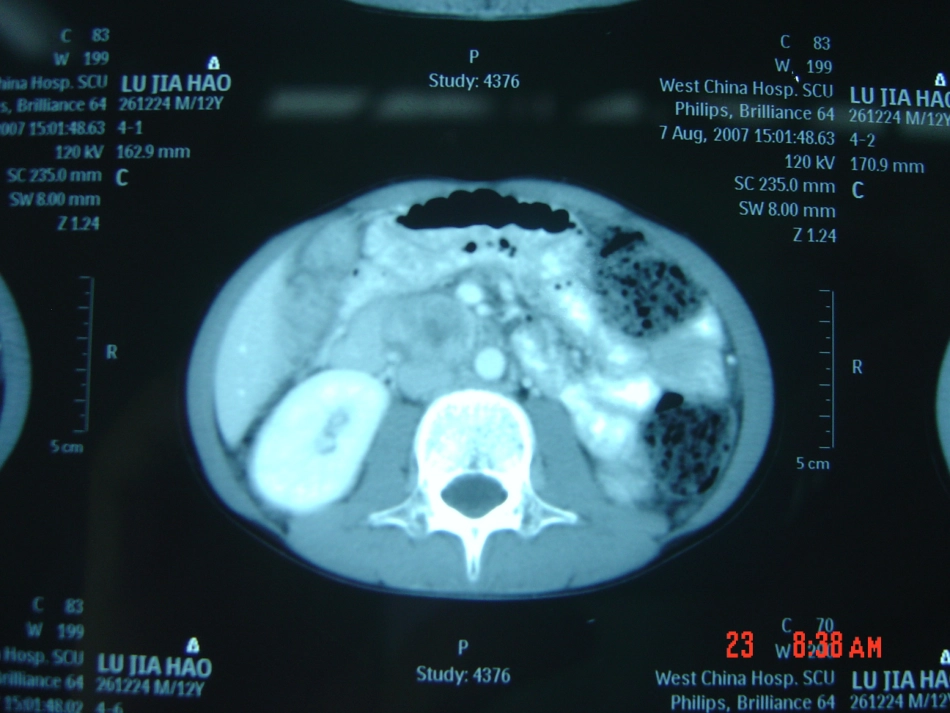

嗜铬细胞瘤麻醉什么是嗜铬细胞瘤嗜铬细胞瘤(pheochromocytoma)起源于嗜铬细胞的肿瘤胚胎早期交感神经元细胞→交感神经母细胞嗜铬母细胞多数嗜铬母细胞→胚胎肾上腺髓质→出生后发育成熟部分嗜铬母细胞(随交感神经母细胞)→椎旁或主动脉前交感神经节→出生后退化并逐渐消失绝大部分嗜铬细胞瘤发生于肾上腺髓质肾上腺外的嗜铬细胞瘤可发生于自颈动脉体至盆腔的任何部位,但主要见于颈动脉体、腹主动脉旁的交感神经节,以及胸腔、膀胱旁等部位。“嗜铬的副神经节瘤”或异位嗜铬细胞瘤。基本病理生理改变嗜铬细胞瘤能自主分泌儿茶酚胺去甲肾上腺素:α受体肾上腺素:α、β受体血管长期处于收缩状态,血容量严重不足临床表现可见于任何年龄,但多见于青壮年,高发年龄为20~50岁,患者性别间无明显差别。临床症状多变,可产生各种不同的症状,最常见的是高血压、头痛、心悸、出汗一)心血管系统表现(一)高血压:最主要的症状,有阵发性和持续性二型1、阵发性高血压型:特征性表现。常有诱因,伴随其他症状,严重者可发生心、脑血管意外。2、持续性高血压型:可多年被误诊为原发性高血压(二)低血压、休克:预后常较恶劣(三)心脏表现:儿茶酚胺心肌病--局灶性心肌坏死,病理特点为心肌收缩带坏死,临床特点类似心肌梗死。不宜使用洋地黄治疗二)代谢紊乱基础代谢增高,糖代谢紊乱,脂代谢紊乱,等三)其他表现:消化系统,泌尿系统,其他麻醉前准备与评估一)麻醉前准备α-肾上腺素受体阻滞剂的应用是麻醉前准备最重要和基本的内容。1、控制血压:最常用药物为酚苄明(phenoxybenzamine),是长效的α1受体阻滞剂。哌唑嗪,钙通道阻滞剂2、纠正心律失常:在使用α受体阻滞剂后,加用β受体阻滞剂最重要的就是评估术前扩血管、扩容治疗是否有效和充分。常用的临床判断标准:1、血压下降并稳定于正常水平,无阵发性血压升高、心悸、多汗等现象,2、体重增加,3、轻度鼻塞,4、四肢末梢发凉感消失或感温暖,甲床由苍白转为红润,5、红细胞压积下降<45%,二)麻醉前评估四、麻醉管理四、麻醉管理一)麻醉前用药:二)麻醉方法:全麻×:氟烷、地氟烷、潘库溴铵、筒箭毒碱、琥珀胆碱三)术中管理主要变化或危险是急剧的血流动力学改变,血压急升骤降和心律失常(一)手术室内麻醉前准备两条快速静脉通道(含中心静脉)有创动脉压、中心静脉压,必要时放置肺动脉漂浮导管床旁血气分析、血糖检测手术室内应备有可正常使用的除颤器。常规准备血管活性药物:酚妥拉明(推荐使用方法:浓度1mg/ml,单次1-5mg。)、艾司洛尔(浓度5mg/ml,单次0.5mg-1mg/kg,持续输注50g-200g/kg/min)、硝普钠(持续输注0.5g-1.5g/kg/min)、去甲肾上腺素(单次0.1g-0.2g/kg,持续输注0.05g-1g/kg/min)、肾上腺素(单次0.1g-0.2g/kg,持续输注0.05g-1g/kg/min),必要时利多卡因、胺碘酮等。(二)容量治疗术前有效的扩容治疗并不能完全满足术中需求,在肿瘤全部静脉被切断前必须恰当进行预扩容一般情况下除补充禁食、禁水、肠道准备的丢失、生理需要量、第三间隙转移、出血量等以外,用于扩容的量大约要达到病人血容量的20-30%(500-1500ml左右,根据病人具体情况需要灵活调整,有些病人需要量可能更大),在肿瘤静脉全部切断前均匀输入(三)循环状况调控:药物+观察与沟通1、高血压:①麻醉诱导期②手术期③严重缺氧或有二氧化碳蓄积探察、分离肿瘤时对瘤体的挤压,当出现与之同步的血压迅速上升,不能长时间等待观察。迅速根据情况采用酚妥拉明1-5mg静脉注射,硝普钠微量泵输人,先从0.5g/kg/min的剂量开始,根据血压高低再随时调整2、心律失常:艾司洛尔,美托洛尔,普萘洛尔(心得安),利多卡因,胺碘酮艾司洛尔,单次0.5mg-1mg/kg,持续输注50g-200g/kg/min美托洛尔,单次1-5mg缓注,5分钟后可重复,总量<15mg普萘洛尔,单次3-5mg缓注,5分钟后可重复,总量<25mg利多卡因,50-100mg缓注,1.5-2mg/min滴注,总量<4mg/kg胺碘酮,75-150mg稀...